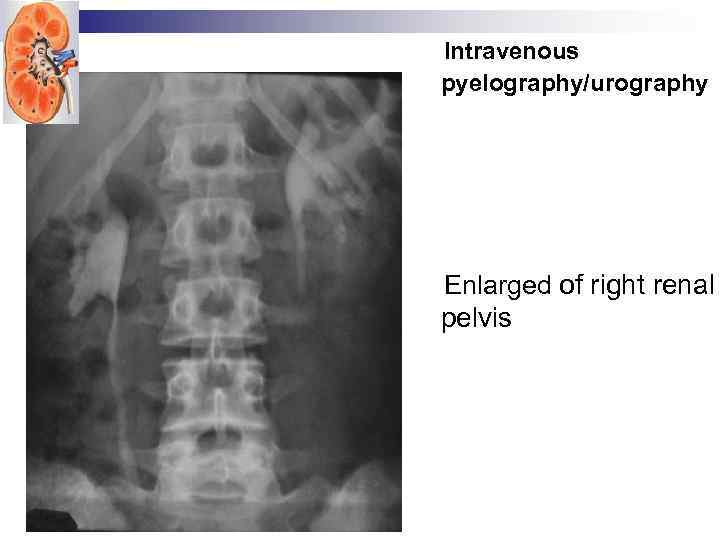

Intravenous pyelography/urography

Intravenous pyelography/urography

Intravenous pyelography/urography Enlarged of right renal pelvis

Intravenous pyelography/urography Enlarged of right renal pelvis